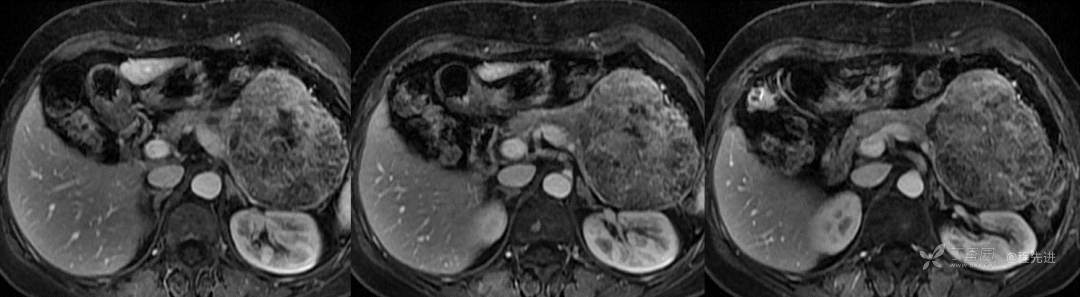

延迟期

汇总对比